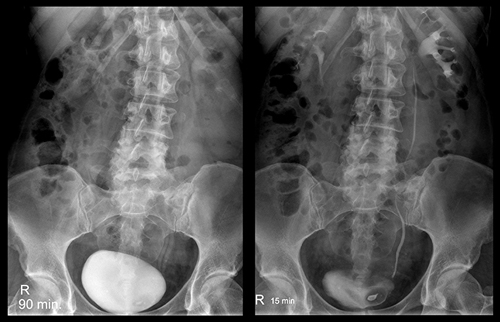

Экскреторная урография при нефроптозе: диагностические изображения